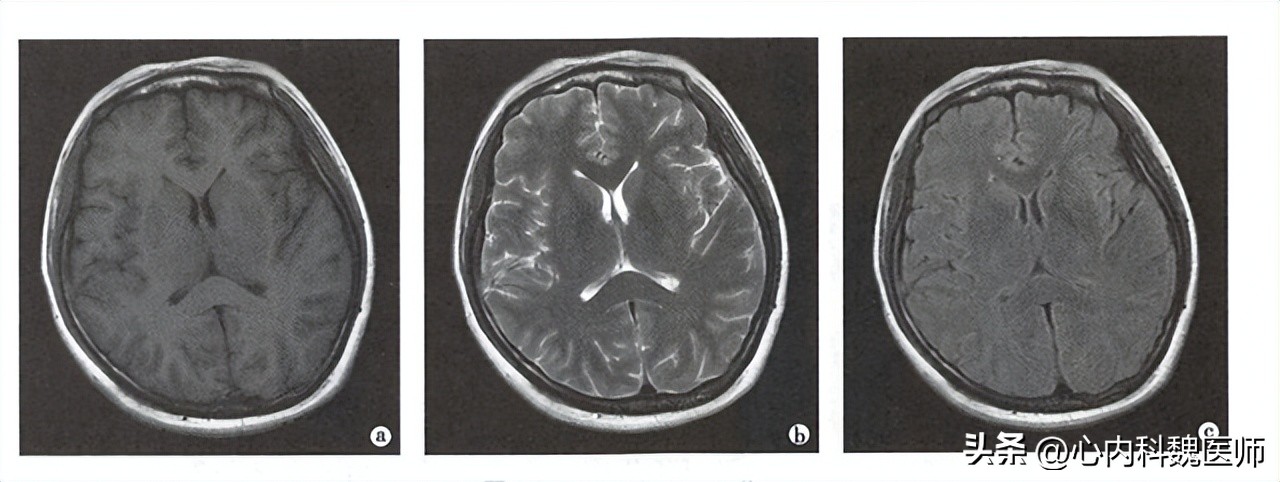

最后,结束射频这个力量,氢质子运动方向恢复的时间,经过计算机分析得到的黑白灰三个不同程度的显影,就是磁共振结果我们看到的图像,我们可以根据颜色的深浅,来判断疾病的发展程度。

其次磁共振可以对血液的特殊显影,迅速在脑部扫描后很快显影效果,如:脑出血、脑梗死等,对位置判断和出血、梗死范围都可以迅速定位。